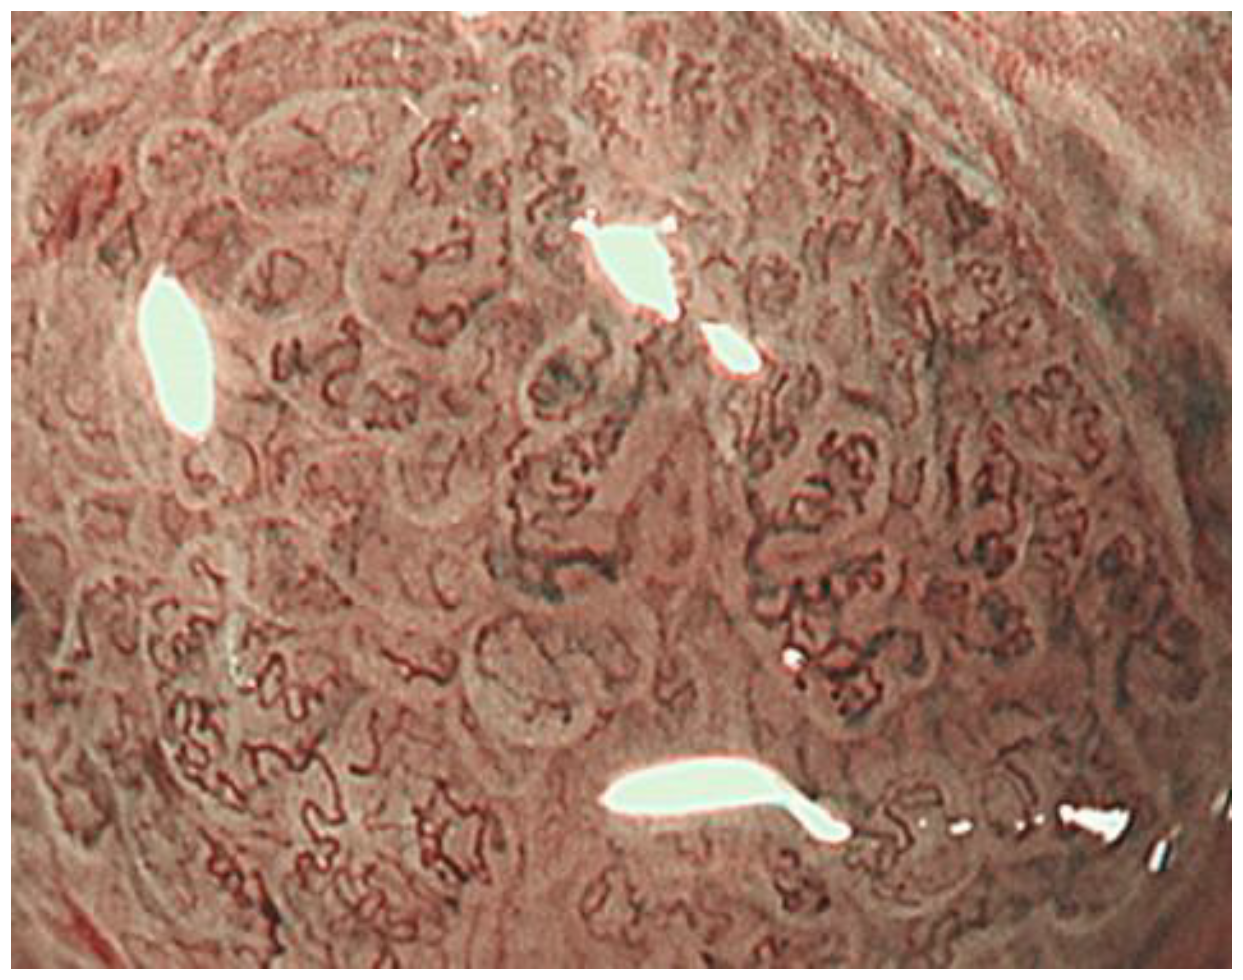

- Kanemitsu, T.; Yao, K.; Nagahama, T.; Fujiwara, S.; Takaki, Y.; Ono, Y.; Matsushima, Y.; Matsui, T.; Tanabe, H.; Ota, A.; et al. The vessels within epithelial circle (VEC) pattern as visualized by magnifying endoscopy with narrow-band imaging (ME-NBI) is a useful marker for the diagnosis of papillary adenocarcinoma: A case-controlled study. Gastric Cancer Off. J. Int. Gastric Cancer Assoc. Jpn. Gastr. Cancer Assoc. 2014, 17, 469–477. [Google Scholar] [CrossRef] [PubMed] [Green Version]